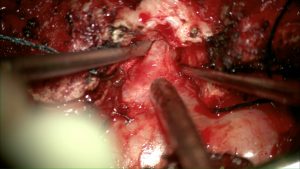

Abordaje longitudinal con esqueletización L2-L4 derecha; disección del componente extracanal del tumor; se aprecia relación con apófisis transversa L3 derecha

Tras exéresis de la apófisis transversa L3

Prefiero resecar de fuera a adentro; en la imagen se aprecia detalle de la raíz tras artrectomía parcial que marca límite medial del tumor, (por lo que se evita exponer más contenido intradural del canal y, en la mayoría de casos, sin salida de LCR).

Tras exéresis tumor procedemos a revisar muñón proximal; en caso de no apreciar morfología radicular o seguir el tumor un crecimiento hacia el espacio subaracnoideo, completaría exéresis hueso (para y lamina/s) y apertura dural.